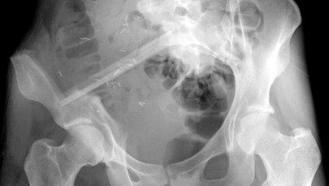

vermelden. Ich erinnert euch alle an die Bilder, die wir euch nach der Operation gezeigt haben. Hier ist es auf dem Foto noch einmal zu

sehen. Es ist ihr operativ das rechte Wadenbein aus dem Bein entfernt und als Stütze in das Becken eingesetzt worden, dort, wo vorher

die Beckenschaufel war. Das ist schon ein Meisterwerk ärztlicher Kunst gewesen. Und Gott hat Gelingen und Segen dazu gegeben. Die

Schmerzen, die Puschel in den letzten Tagen mehr hatte als sonst, rühren jetzt daher, dass der Knochen etwa an der Stelle, auf die der

Pfeil zeigt, richtiggehend durchgebrochen ist. Die Ärzte sprechen von einem Ermüdungsbruch. Der Knochen ist in der Substanz während

der Zeit der Chemo und der dadurch beabsichtigten Verhinderung der Neubildung von Zellen (Zielpunkt waren natürlich die

Krebszellen) zurückgegangen und ermüdet. Das große Problem ist, dass nun noch weniger Stabilität da ist und der Knochen erst wieder